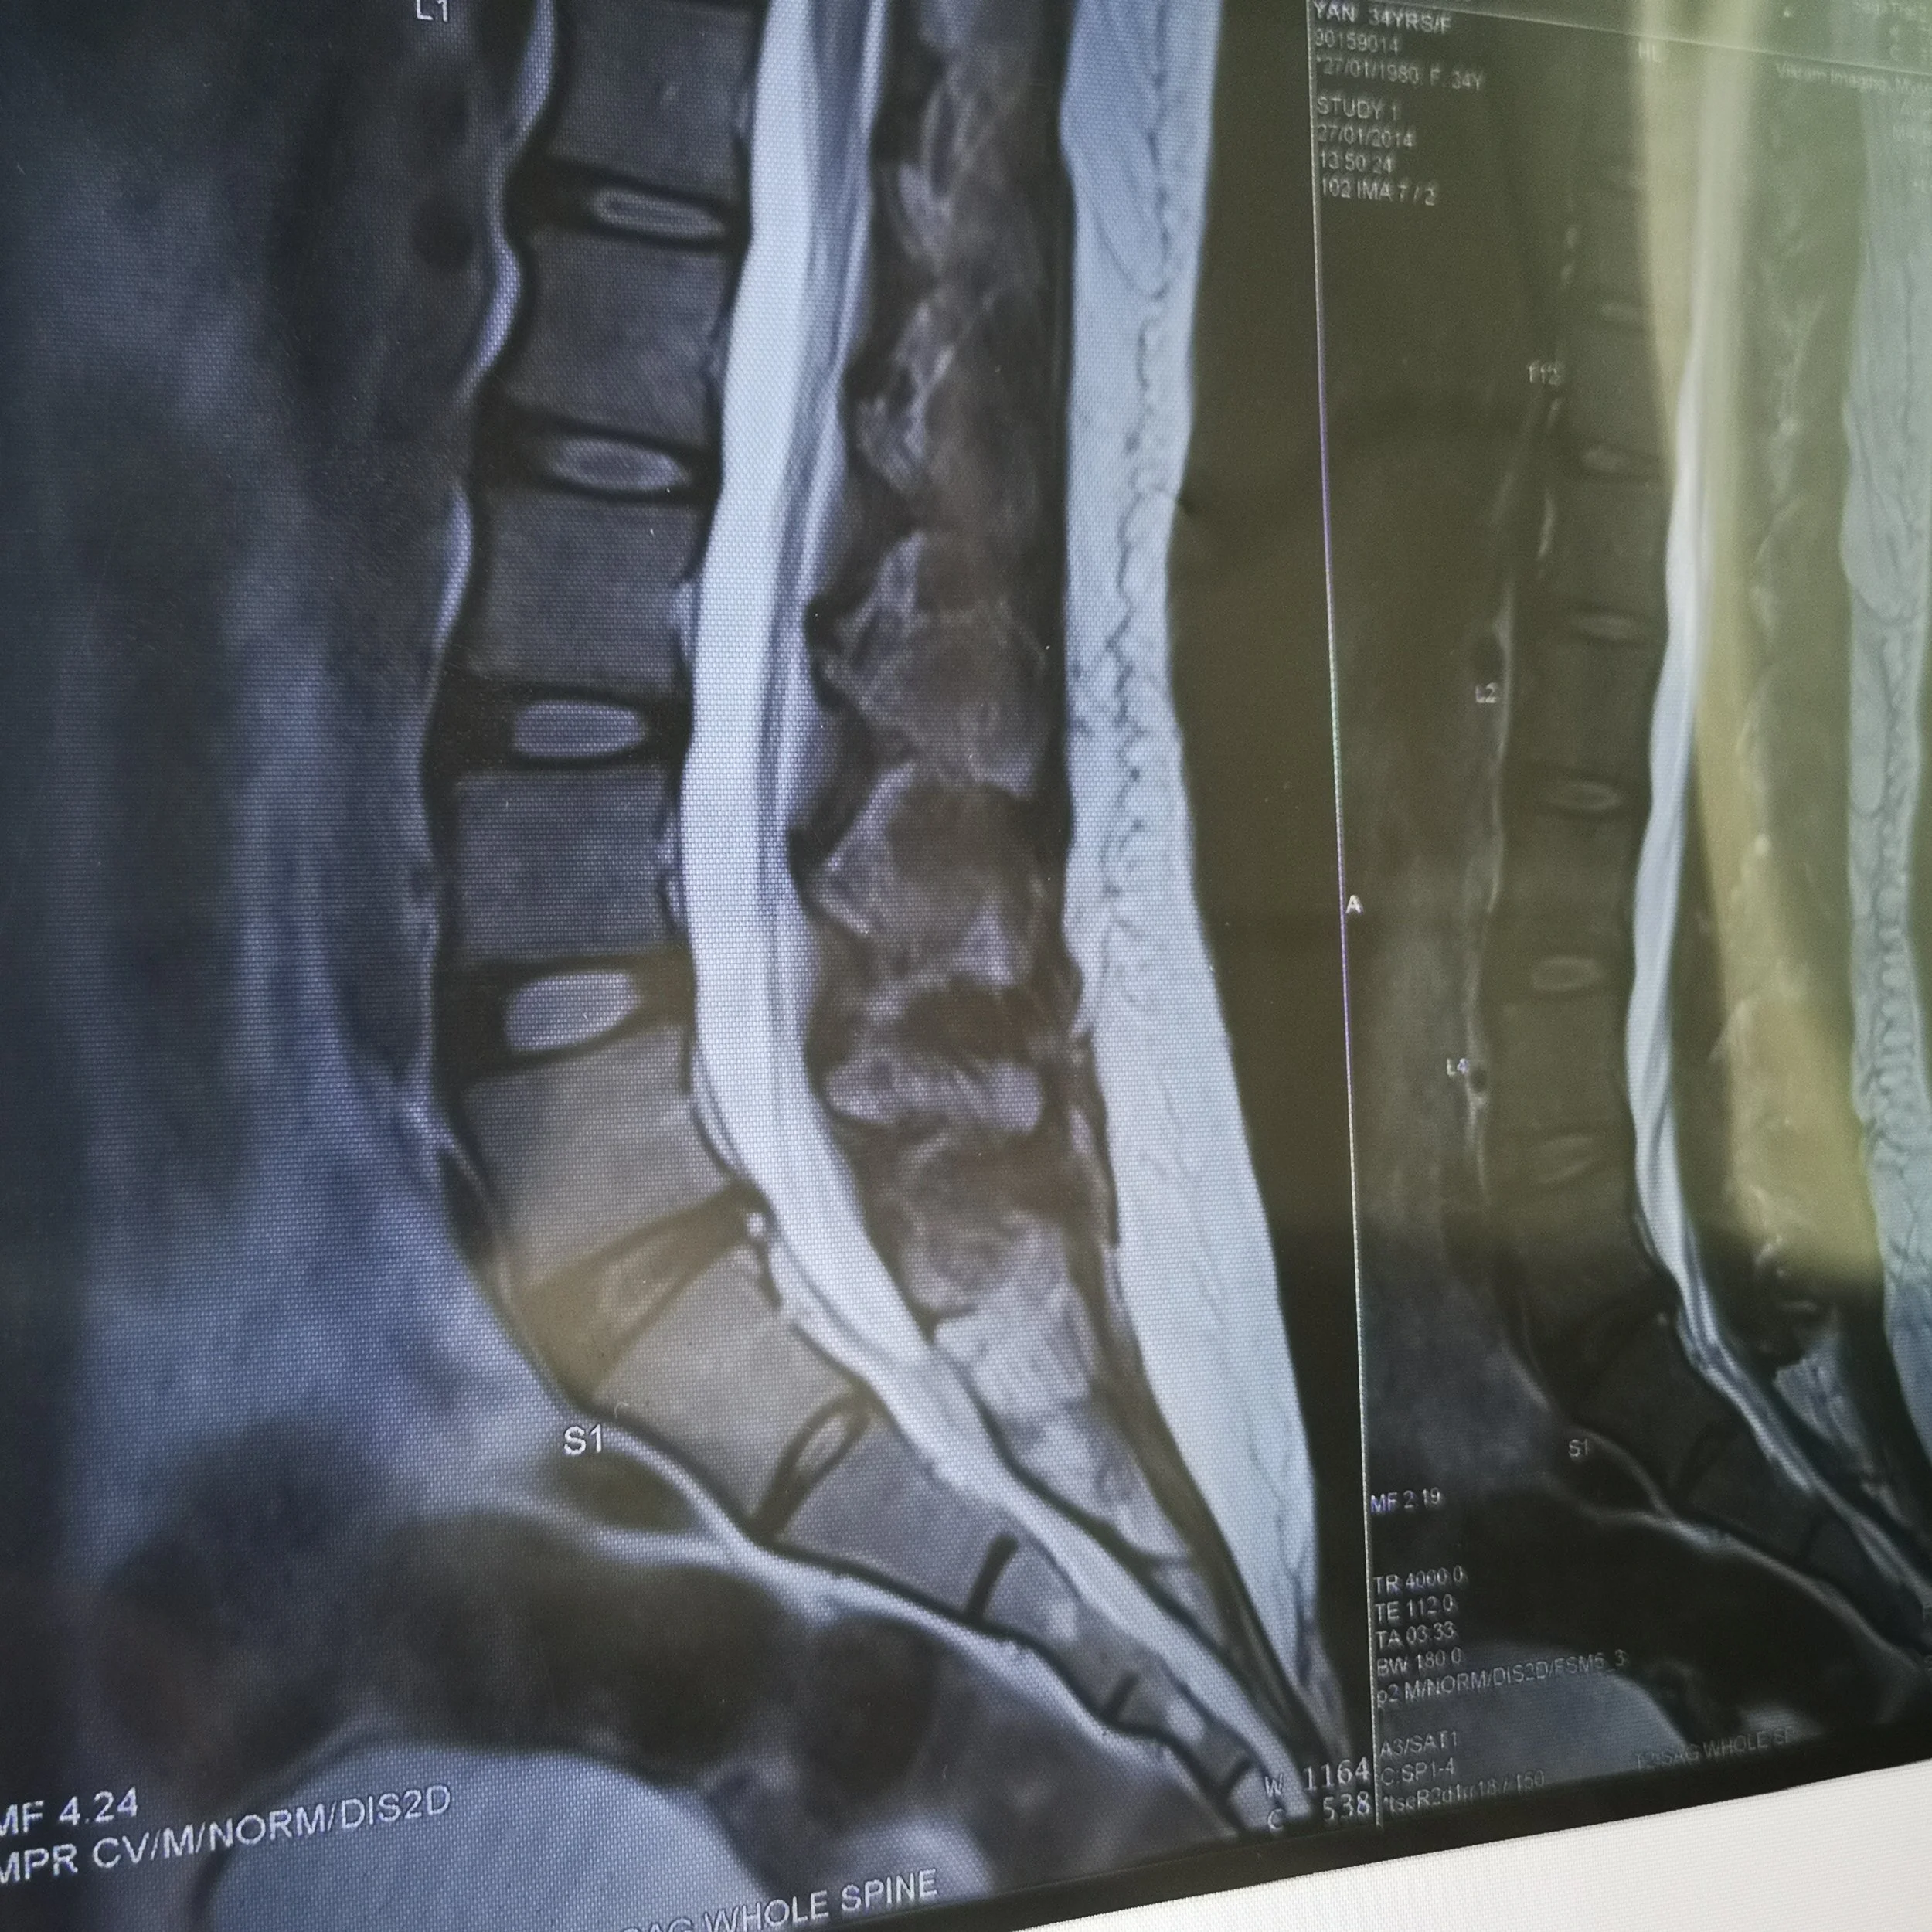

Just before I flew out, I did another MRI, and it said the same place where I had a herniated disc was now herniated in 2 locations on the same disc.

MRI 2 in 2017. Now with para central annual disc bulge causing bilateral foramina narrowing & abutting bilateral traversing S1 nerve roots, in addition to previous posterocentral herniation.